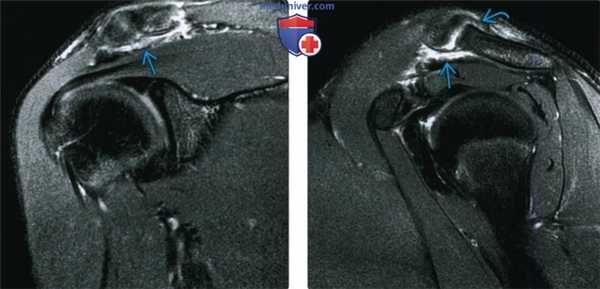

Рис.2А Т2-ВИ FS, лизис субхондральной костной ткани акромиального конца ключицы с формированием кистозных включений (головка стрелки) с относительной сохранностью акромиона (изогнутая стрелка).

Рис.2Б Т1-ВИ, лизис субхондральной костной ткани акромиального конца ключицы (изогнутая стрелка) с формированием кист (головка стрелки).